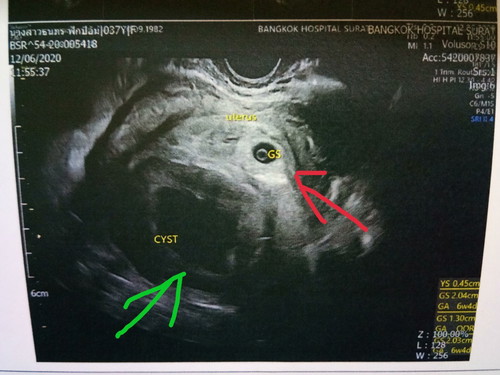

เป็นซีสขนาดใหญ่ 7 ซม. คุณหมอบอกรอดูถ้าไม่ยุบ อาจต้องผ่าตัดระหว่างตั้งครรภ์ (สีแดงคือการฝั่งตัวของไข่ สีเขียวคืถุงน้ำหรือซีส)